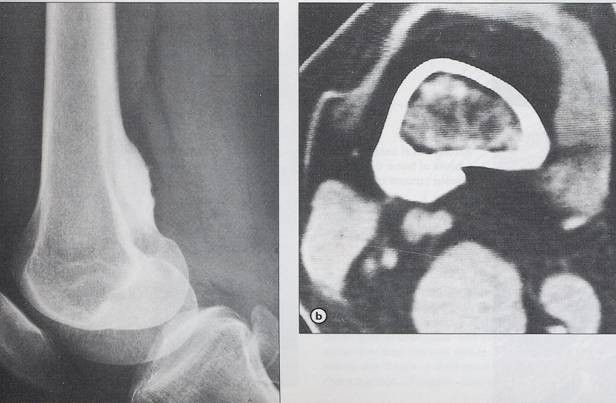

Chondrosarcom

b)humerus dr

proximal, distructie corticala, extensie in parti moi